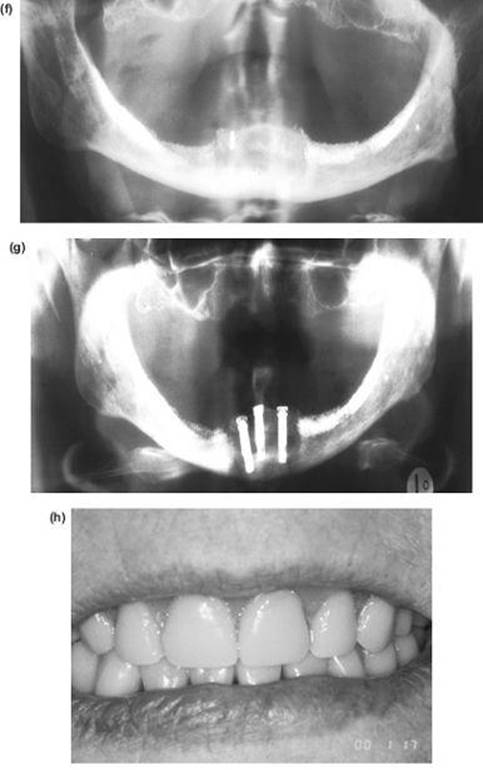

7. The nasal septum and pterygoid plates are separated intraorally, as in the Le Fort I operation.

8. If distraction osteogenesis is not being used, mobilisation is carried out extraorally from above and behind the head (“slowly but strongly”) with the Rowe's disimpaction forceps. Both a forward tilting and transverse rotation are required to achieve a completely mobile skeletal block. Intraoral traction with Tessier's maxillary retractors is also important.

9. Temporary intermaxillary fixation is applied, using an intermediate wafer in a bimaxillary case. The bone grafts are inserted at the osteotomy sites. The most important one is the malar cut, which is wedged open as shown in Figure 9.14 and fixed with bone plates.

10. All sharp bony margins are carefully masked with spare can-cellous bone or smoothed with an acrylic bur.

11. At this stage the intermaxillary fixation is removed and, where necessary, the mandibular osteotomy completed, drains inserted and the intraoral wounds sutured.

12. The pharynx is sucked out and the pack removed.

13. The blepharoplasty wounds are closed after the insertion of miniature vacuum drains, with subcuticular 5/0 Prolene sutures.